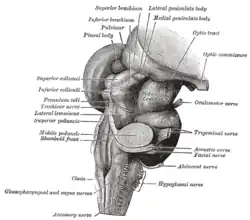

Hirnnervenfunktion: Es gibt zwölf Hirnnervenpaare. Die Funktion jedes Hirnnerven kann in einer neurologischen Untersuchung geprüft werden. Da dies sehr aufwändig ist, werden Hirnnerven meist nur „orientierend“ untersucht. Das heißt, man macht eine unvollständige Untersuchung unter der Annahme, dass wahrscheinlich alles in Ordnung ist. Wenn jedoch eine Hirnnervenstörung vermutet wird, muss im Zweifelsfall jede einzelne Funktion genau geprüft werden. Die ersten beiden Hirnnerven sind der Nervus olfactorius für den Geruchssinn und der Nervus opticus für den Sehsinn. Das Riechen wird mit Riechstoffen geprüft (z. B. mit Kaffeepulver) und das Gesichtsfeld mittels der sogenannten Fingerperimetrie. Die Hirnnerven III, IV und VI steuern die Bewegungen der Augen (Bewegung eines Fingers des Arztes verfolgen). Der fünfte Hirnnerv ist der Nervus trigeminus. Er versorgt sensibel das Gesicht und motorisch die Kaumuskulatur. Der Nervus facialis ist der siebte Hirnnerv. Er versorgt motorisch die mimische Muskulatur. Der achte Hirnnerv ist für Gehör- und Gleichgewichtsorgan zuständig. Hier kommt der Stimmgabeltest zur Anwendung. Den Gleichgewichtssinn prüft man sinnvollerweise nur, wenn er gestört ist. Die Patienten haben dann ein Schwindelgefühl. Zu diesem Zweck gibt es spezielle Methoden, mit denen man Schwindel provozieren kann. Der neunte Hirnnerv ist der Nervus glossopharyngeus. Er hilft beim Schlucken und vermittelt auch den Geschmack im hinteren Zungendrittel (dort schmeckt man bitter). Der zehnte Hirnnerv ist der Nervus vagus, er vermittelt die vegetative parasympathische Innervation der inneren Organe. Er versorgt sensorisch außerdem die Ohrmuschel und motorisch das Gaumensegel. Der elfte Hirnnerv steuert einen Teil der Nackenmuskulatur und der zwölfte Hirnnerv (Nervus hypoglossus) bewegt die Zunge.

Die alte Dame mit der Sprechstörung hat eine so genannte „gekreuzte“ Symptomatik: das herabhängende Oberlid rechts (ein Horner-Syndrom) und die Störung der Temperatursensibilität links. Eine „gekreuzte“ Symptomatik ist aufgrund anatomischer Verhältnisse typisch für den Hirnstamm. Die hintere kleine Kleinhirnarterie ist häufig betroffen.

Die alte Dame mit dem Hirnstamminfarkt ist ein Musterbeispiel für die so genannte topische Diagnostik in der Neurologie. Die Kombination eines Hornersyndroms mit einer kontralateralen Störung der Temperaturempfindlichkeit deutet immer auf den Hirnstamm und dort in den Bereich der Medulla oblongata. Entscheidend für das Verständnis der Störung ist, dass im Bereich des Hirnstamms einerseits Kerngebiete der Hirnnerven liegen und andererseits Bahnen für Motorik und Sensibilität. Die enge Nachbarschaft dieser Strukturen an dieser Stelle im Gehirn führt zu Störungen in weit entfernten Körperteilen, die von diesen Strukturen versorgt werden.